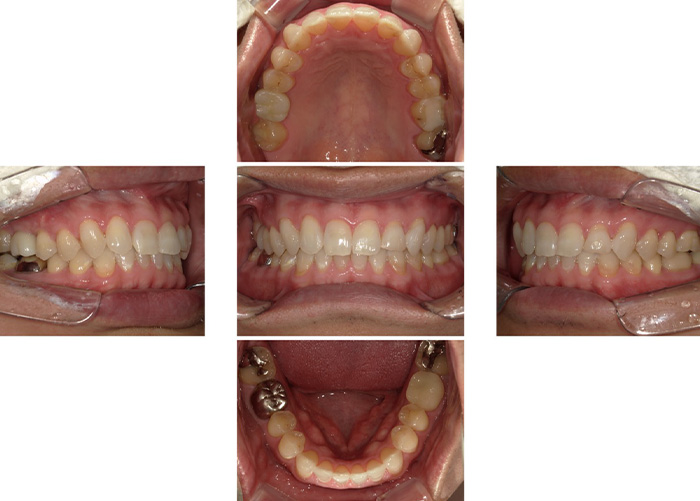

Case.03

![]() ![]() |

|---|

| 主訴 | 上の歯が全部ぐらぐら動く |

|---|---|

| 治療期間 | 12か月 |

| 治療費 | 3,000,000円(税込3,300,000円)(ALL ON 4) |

| 治療内容 | 4本のインプラントで上の歯をすべて補う治療法です。 抜歯をしたその日に仮歯を入れることも可能です。 |

| 治療のリスク | 一時的な鼻出血、内出血、眼出血、上顎洞炎、腫脹のリスクがあります。 |